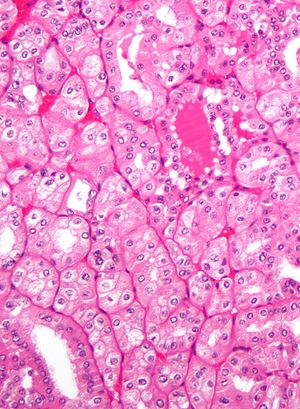

Micrograph showing the most common type of kidney cancer (clear cell renal cell carcinoma). H&E stain. | |

The most common type of kidney malignancy is renal cell carcinoma,[11] which is thought to originate from cells in the proximal convoluted tubule of the nephron.[9][12] Another type of kidney cancer although less common, is transitional cell cancer (TCC) or urothelial carcinoma of the renal pelvis.[13] The renal pelvis is the part of the kidney that collects urine and drains it into a tube called the ureter.[13] The cells that line the renal pelvis are called transitional cells, and are also sometimes called urothelial cells. The transitional/urothelial cells in the renal pelvis are the same type of cells that line the ureter and bladder. For this reason TCC of the renal pelvis is distinct from RCC and is thought to behave more like bladder cancer.[13] Other rare types of kidney cancers that can arise from the urothelial cells of the renal pelvis are squamous cell carcinoma and adenocarcinoma.[9]